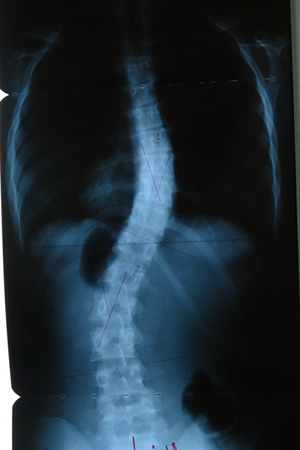

Grafilerle Skolyoz